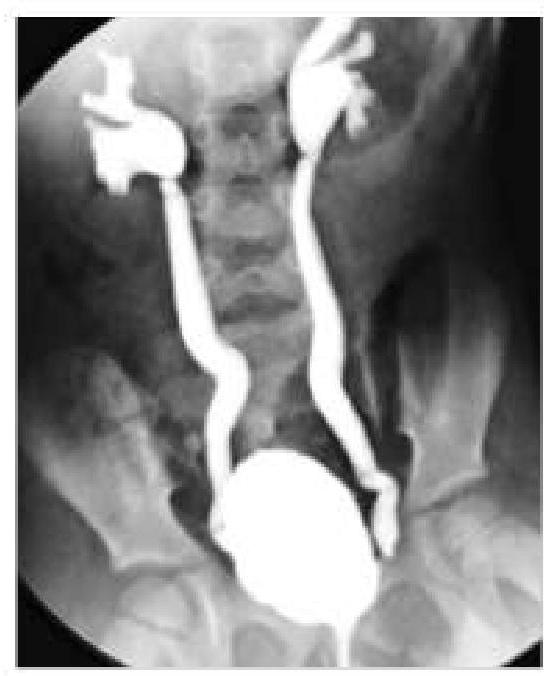

A 6-year-old boy came with a history of recurrent urinary tract infections. Imaging was done and showed retrograde flow of urine from the bladder into the ureters. What is the most likely diagnosis based on the imaging findings?

Explanation: ***Vesicoureteric reflux (VUR)*** - VUR is defined by the **retrograde flow of urine from the bladder into the ureters**, which directly matches the imaging finding described - This is the **most common cause of recurrent UTIs in children**, as reflux allows bacteria to ascend from the bladder to the kidneys - Diagnosed by **voiding cystourethrogram (VCUG)**, which shows contrast refluxing into ureters during micturition - Graded from I to V based on severity; can lead to **reflux nephropathy** and renal scarring if untreated *Urinary bladder diverticulum* - An **outpouching of the bladder wall** through weakened muscle layers - May predispose to UTIs due to urinary stasis within the diverticulum, but does **not cause retrograde flow into ureters** - Imaging would show a **saccular projection** from the bladder, not ureteral filling *Vesicocolic fistula* - An **abnormal communication between bladder and colon**, typically from inflammatory bowel disease, malignancy, or trauma in adults (rare in children) - Presents with **pneumaturia (air in urine)**, fecaluria, and recurrent UTIs - Would not demonstrate **retrograde ureteral flow** on imaging *Urinary bladder hernia* - Protrusion of bladder through a **hernial defect** (inguinal, femoral, or abdominal wall) - Presents as a **reducible mass** that may increase with Valsalva - Does not cause **ureteral reflux** and has a distinct clinical and radiological presentation